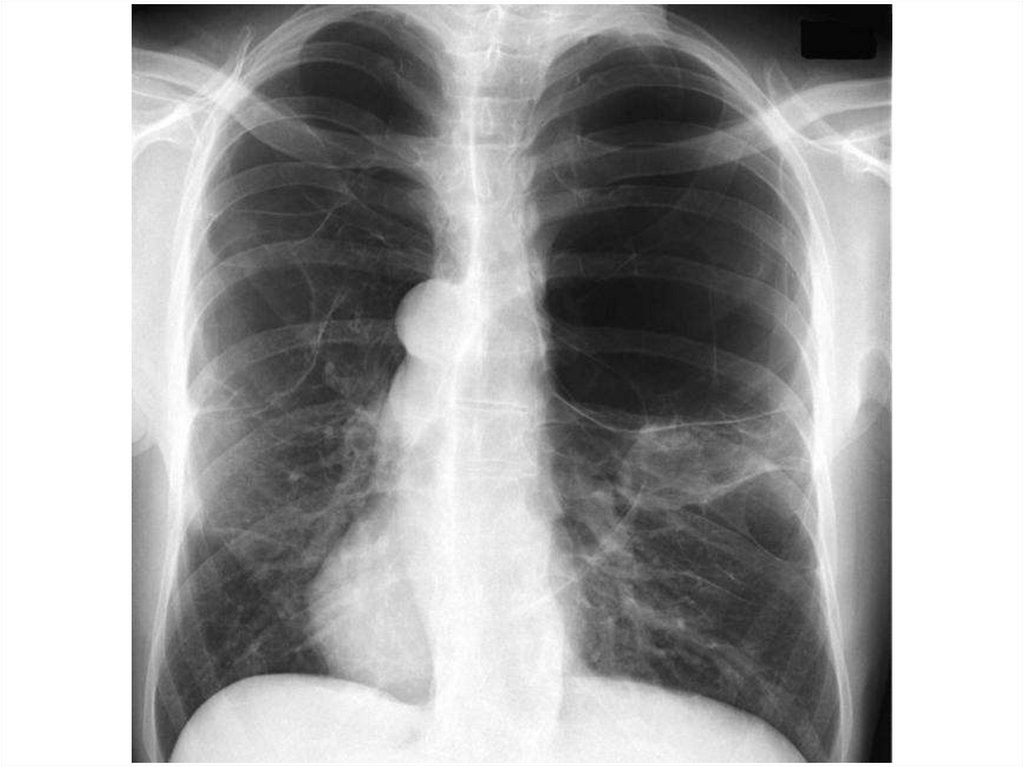

15. Наличие воздуха в плевральной полости

В большинстве случаев пневмоторакс - это

односторонний процесс. Может возникнуть в

результате травмы извне, либо спонтанно при

деструктивных процессах в легких. Имеет 3

механизма – открытый, закрытый, клапанный

(напряженный).

Видимая картина – поджатое к корню легкое,

смещение средостения в другую сторону.

Одностороннее просветление на стороне

поражения.